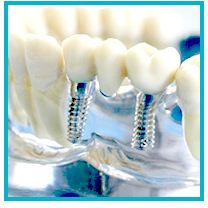

Kaybedilen dişlerin yerine tedavi amacı ile yerleştirilen ve organizma için herhangi bir yan etkisi olmayan, kemik dokusu ile birleşimini tamamladıktan sonra da doğal bir diş gibi iş görebilen, titanyumdan yapılmış; plak, vida ve çivilere implant denir.

Günümüzde implant materyali olarak en fazla kullanılan metal titanyumdur. Titanyum, doku uyumu mükemmel olan, yüzyıllardır tıbbın birçok alanında güvenle kullanılan bir metaldir.

Kök, silindir ya da vida şeklinde biçimlerindirilen titanyum, özel birtakım işlemlerden geçirildikten (özel tasarım asitleme, lazerle pürüzlendirme vb.) sonra dental implant olarak kullanıma hazır hale gelmektedir. Bu işlemler implantın kalitesini belirler.